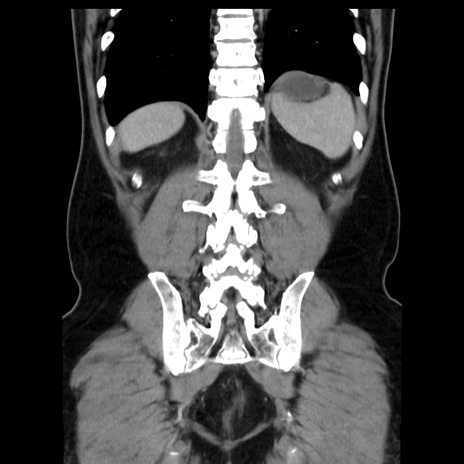

症例16(冠状断像)

【症例】 70歳代男性

【主訴】 腹痛、嘔吐

【現病歴】 約1ヶ月前より間欠的に腹痛と嘔吐あり、当院消化器内科を受診したところCTで多発する肝臓のLDAを指摘され、精査中であった。以降は消化器症状は安定していたが、2日前より嘔気と腹痛があり、同日より排便・排ガスが消失した。改善認めず、 本日、救急外来を受診した。

【既往歴】 大腸ポリープ切除後。

【身体所見】意識清明・会話良好、BT 36.3℃、BP 127/80mmHg、 P 80bpm、腹部:膨満あり、平坦・軟、上腹部正中および下腹部正中に圧痛あり、反跳痛なし、筋性防御なし。

【データ】WBC 7200、CRP 0.77